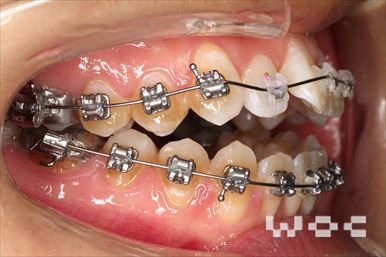

出っ歯上のみ舌側矯正、下はエッジワイズ装置

上は舌側矯正で希望。第一選択は上顎両側第一小臼歯の抜歯だったが、ボーダーラインケースであり改善なければ抜歯することを了承のうえ、非抜歯治療で開始。非抜歯で終了しました。

- 年齢:28歳女性

- 主訴:出っ歯、前歯が曲がっているのが気になる

- 基本矯正料金:103万円

- 治療期間:1年8ヶ月

- 非抜歯